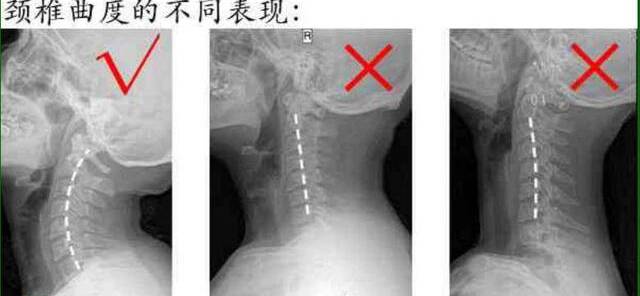

李濤院長表示,在得頸椎病的年輕人中,大多數(shù)可能還有頸椎生理曲度的變直、反弓,由于現(xiàn)代工作壓力增大及手機(jī)等智能設(shè)備的普及,長時(shí)間的低頭導(dǎo)致頸椎間盤壓力增大,出現(xiàn)頸椎間盤疾患,引起頸肩部疼痛、肢體麻木、放射痛、行走不穩(wěn)等癥狀。